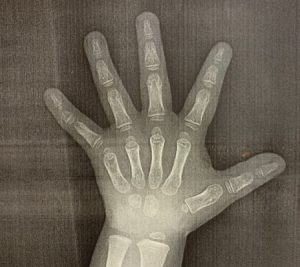

3)左手のレントゲン撮影

そして、骨年齢を知るために手のレントゲンを撮影しました。

これは、年齢相応の骨の数や形あるとの事で、

成長ホルモンの分泌不足で、骨年齢が暦年齢より著しく遅れている

かどうかを知るためだそうです。

また、骨年齢の成熟度から、あとどれくらい身長が伸びるかも

わかると先生から説明を受けました。

【骨のX線検査】

やはり実年齢より骨の発育が1歳ほど幼いと言われました。。。

ただ、許容範囲のレベルだという事で・・・

骨のX線検査もクリア!